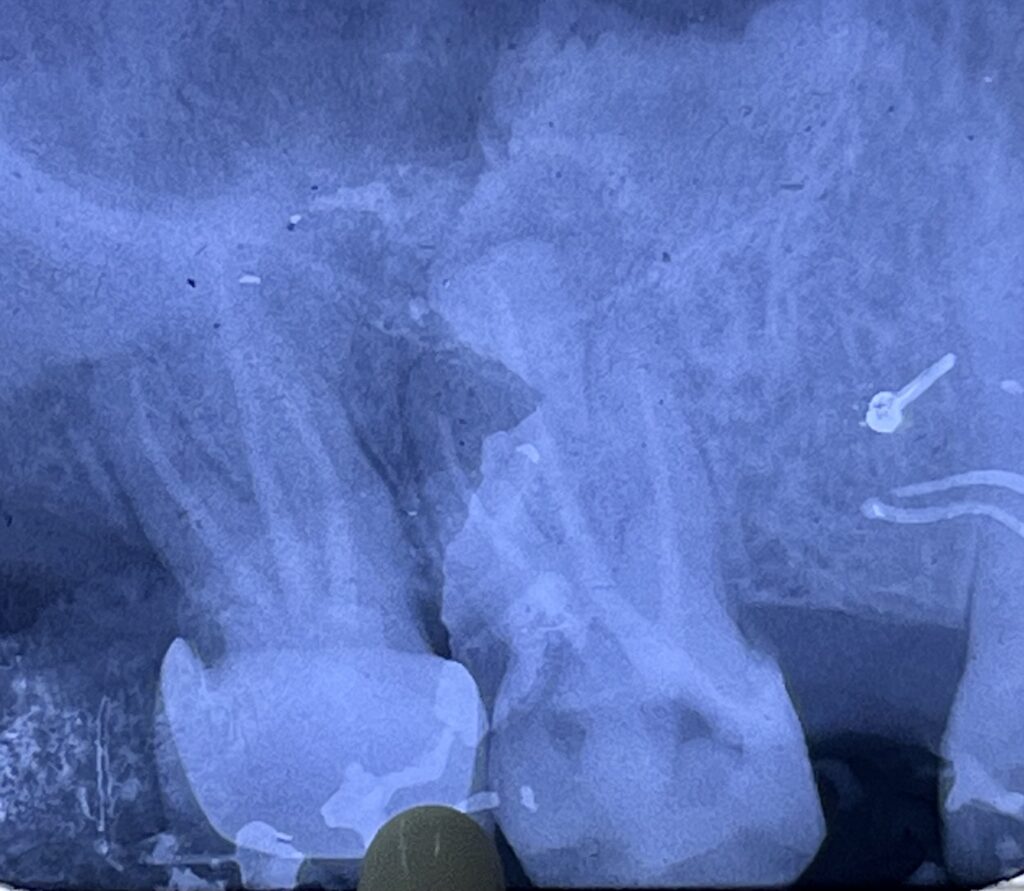

- Endodontically treated posterior tooth

- Moderate to extensive loss of coronal structure

- No signs of acute pathology